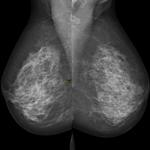

Mammography remains the standard means of screening for breast cancer. For women with denser breast tissue, the superimposition of tissue may mask early tumors even for the most observant of radiologists.

Recently, we wrote about the challenges that women with dense breasts face with mammograms — the primary tool used to screen for breast cancer.